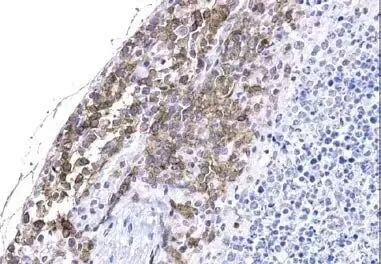

消失的CAR-T细胞 “明明回输了2亿CAR-T细胞,小鼠肿瘤却越长越大!” 张教授盯着实验数据百思不得其解:体外实验时,CAR细胞精准识别并杀光了胃癌细胞;活体实验中,肿瘤组织切片却找不到CAR细胞踪迹。 “细胞究竟去哪了?是迷路了,还是被‘团灭’了?” 为解答这个问题,团队试遍了传统方法: ◾ 定制抗体 → 等了4个月,花费过十万 ◾ RNA原位杂交 → 结果模糊,疑似假阳性 ◾ 流式细胞术 → 只能检测血液中的细胞 “钱和时间砸进去,肿瘤里的CAR细胞依然‘神隐’!” 直到近日在美国癌症研究协会(AACR)年会遇上Cell Signaling Technology(CST)—— “为什么非要盯着CAR的‘脸’(scFv)?所有CAR 都有通用‘身份证’(G4S/Whitlow接头)!” 这句话让团队豁然开朗: ✅ 无需为每种CAR定制抗体 ✅ 一套工具兼容所有基于scFv的CAR ✅ 直接定位实体瘤中的细胞 NEXT 靶向接头序列的“万能钥匙” CST全球创新方案 创 新 ◾ 抛弃“一CAR一抗体”模式! ◾ 独家开发抗CAR接头抗体:瞄准G4S或Whitlow/218接头(CAR分子中的“通用身份证”)。该产品荣获2023 CiteAb 创新奖。 ◾ 兼容多平台:流式、IHC、ELISA、细胞分选。 实体瘤战场:让看不见的CAR 细胞“显形” 肿瘤渗透验证 全球首款IHC-P验证抗体: Witlow/218 Linker(F2G3S)Rabbit mAb #47414 直接在FFPE实体瘤切片中定位CAR细胞,避免RNA原位杂交的假阳性风险 IHC-P:适用#47414对NSG小鼠脾脏中经异种移植的Raji B细胞淋巴瘤进行免疫组织化学分析,该小鼠脾脏中灌注了靶向CD19的原代人类CAR-T细胞 微环境全景解析 SignalStar™多重荧光IHC:同步标记多达8种生物标志物(如CAR细胞+CD8+T细胞+癌细胞等) 助您看清“CAR细胞如何与肿瘤微环境的对话” SignalStar™Oligo-Antibody Pair 组合(左),缓冲液试剂盒(右) 简化的CAR细胞检测 开发特异、灵敏的抗独特型抗体来检测 CAR工程化细胞可能会是一个漫长且耗费资源的过程。CST专注于该过程中的一个关键步骤,并开发了一套专门用于CAR细胞表征的研究工具。无论您的目标是对CAR工程化细胞进行检测、分析、定量、纯化,还是在转化组织学的背景下对其进行研究,CST®解决方案均可简化您的表征工作流程。 检测:评估 CAR 和靶抗原表达 CAR 检测 CAR 检测对照 靶抗原检测 分析:探究免疫细胞的激活、增殖、 活力和信号转导 T 细胞激活 细胞增殖 细胞毒性 免疫表型分析 下游信号转导解析 定量:定量 CAR 表达和转导效率 测定 CAR 分子的密度 检测 CAR 转导效率 纯化:富集 CAR+细胞 基于微球的分选 基于 FACS 的分选 转化:确定 CAR 工程化细胞是否 进入肿瘤微环境 检测 CAR+ 细胞对组织的渗透 探究肿瘤微环境 认准CST授权一级代理商——基因有限公司 欲了解更多产品详情,请扫码添加您的专属技术顾问,基因有限公司将以热忱与专业,为您提供最优质的服务!